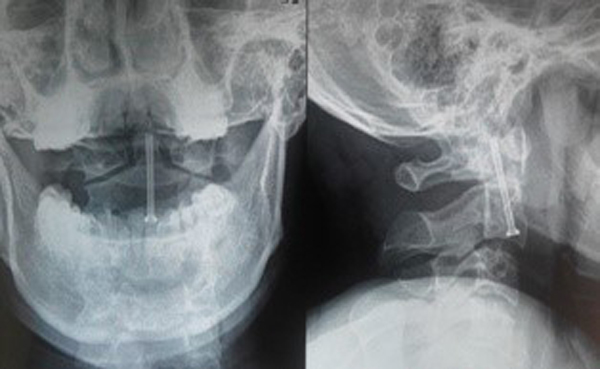

Chẩn đoán hình ảnh: Tất cả bệnh nhân được chụp X Quang quy ước (thẳng, nghiêng, há miệng) và cắt lớp vi tính 64 dãy có dựng hình đánh giá vị trí đường gãy, tình trạng khớp đội – trục bên, khoảng cách di lệch mỏm nha so với thân C2. Chụp cộng hưởng từ phát hiện tổn thương tủy và tình trạng dây chằng ngang.

Chúng tôi tiến hành phẫu thuật vít trực tiếp mỏm nha cho 2 trường hợp qua đường mổ cổ trước, phẫu thuật vít qua khớp C1-C2 cho 2 bệnh nhân qua đường mổ cổ sau.

Tuổi trung bình 28 ± 4,69 tuổi (24 – 33), tất cả bệnh nhân đều là nam giới, nhập viện vì nguyên nhân tai nạn giao thông (1 bệnh nhân) và tai nạn ngã cao (3 bệnh nhân) với cơ chế ngã cắm đầu về phía trước. Trên lâm sàng, tất cả BN không có biểu hiện tổn thương thần kinh, VAS trung bình 6 ± 0,816 điểm (5-7). Chụp X quang quy ước và chụp cắt lớp vi tính 64 dãy dựng hình có tổn thương gãy mỏm nha loại 2.

Đánh giá kết quả sau mổ 1 tháng, tất cả bệnh nhân có chỉ số giảm chức năng cột sống cổ NDI ở mức độ không ảnh hưởng, VAS cải thiện rõ trung bình 1 ± 0,816 (0-2), vận động cột sống cổ bình thường với vít trực tiếp mỏm nha, hạn chế nhẹ với vít qua khớp. Chụp X quang các tư thế, chụp cắt lớp vi tính cột sống cổ cho thấy không có di lệch vị trí đặt vít, không mất vững đội – trục.